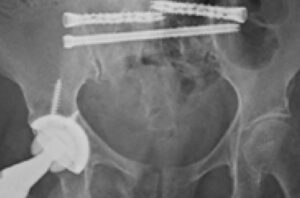

Dr. Brian Cunningham uses two iFuse TORQ TNT® implants for sacral fracture fixation and SI joint fusion following low-energy ground-level falls.